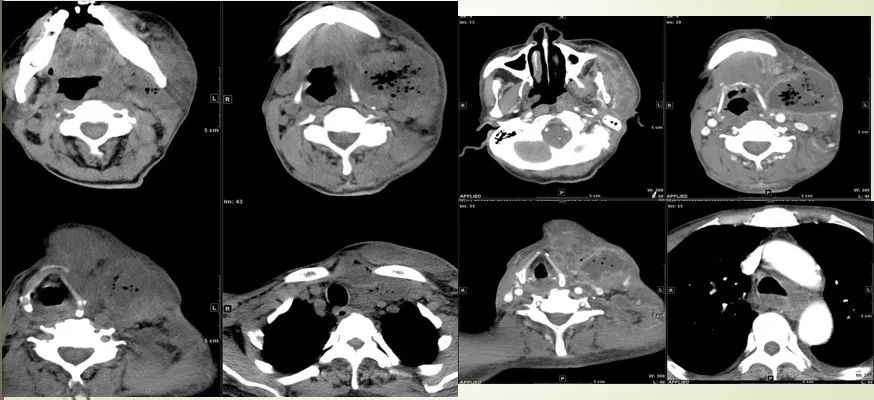

15 多间隙受累

(1)左下后牙疼痛11天余,颈部肿胀10天。

(2)右侧颌面部弥漫性肿胀1月余。